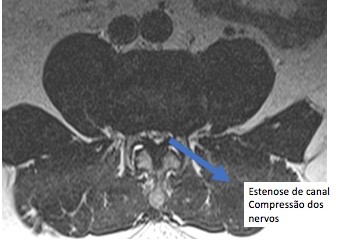

Todo esse processo, junto, de abaulamento, protrusões ou herniações discais com hipertrofia das facetas articulares e espessamento dos ligamentos causa estenose do canal lombar.

O exame padrão ouro para o diagnóstico da estenose de canal lombar é a ressonância magnética da coluna lombar.

Ressonância magnética com estenose de canal lombar em 2 níveis L3L4 L4L5